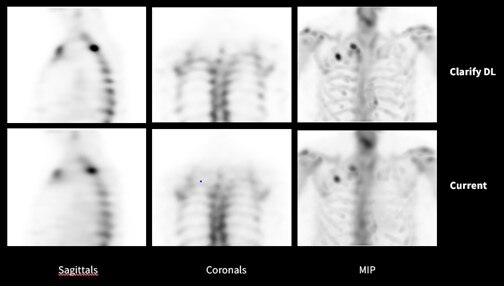

AI*を用いた骨SPECTのノイズ低減技術:Clarify DL

核医学における画像再構成の技術はその歴史とともに進化し、昨今ではBSREM法(画像再構成の演算の中にノイズ抑制のパラメータを加えることでノイズを制御しながら逐次近似再構成を行う技術)などが採用されてきました。今回、GEヘルスケアは新たな技術として骨SPECTにAI*を用いてコントラストと空間分解能を維持しながらノイズを抑制する技術を採用しました。ノイズ低減による更なる高画質化により、臨床的有用性の向上を目指します。

Clarify DLによるノイズ低減技術